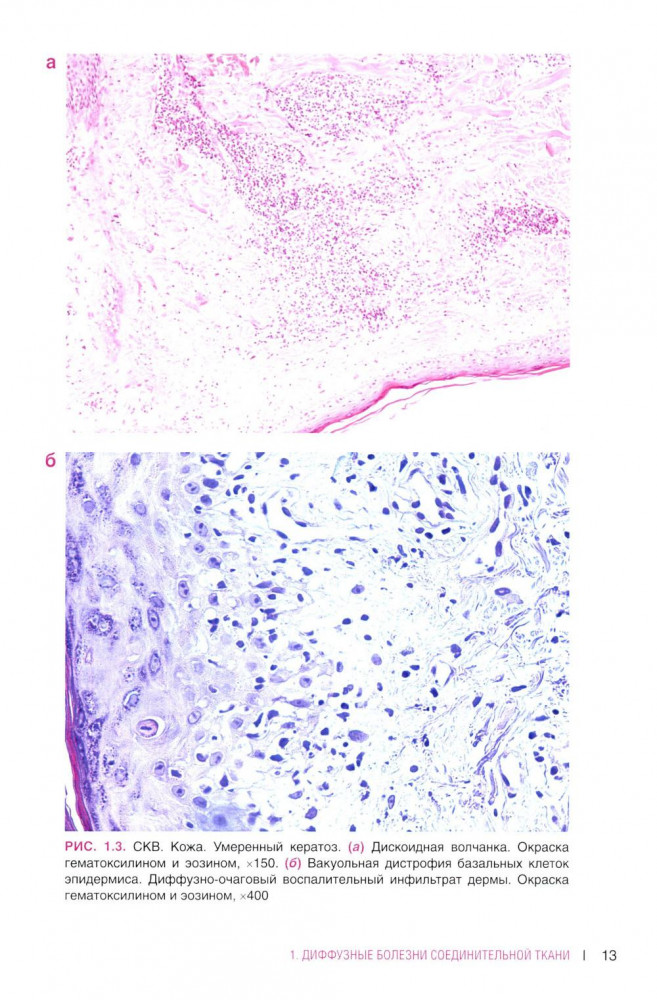

💳 Оплатить за товар можно при получении 🇰🇿 Есть бесплатная доставка по Казахстану от 1 дня 🎁 Копите бонусы с каждой покупки В атласе представлены авторские гистологические иллюстрации различных ревматических заболеваний, включая ревматоидный артрит, системную красную волчанку, системную склеродермию. Включены некоторые редкие патологии, такие как склеро-микседема, lgG-ассоциированное заболевание, панникулиты, аутовоспалительный синдром, ассоциированный адъювантами. Широко представлены системные васкулиты. |